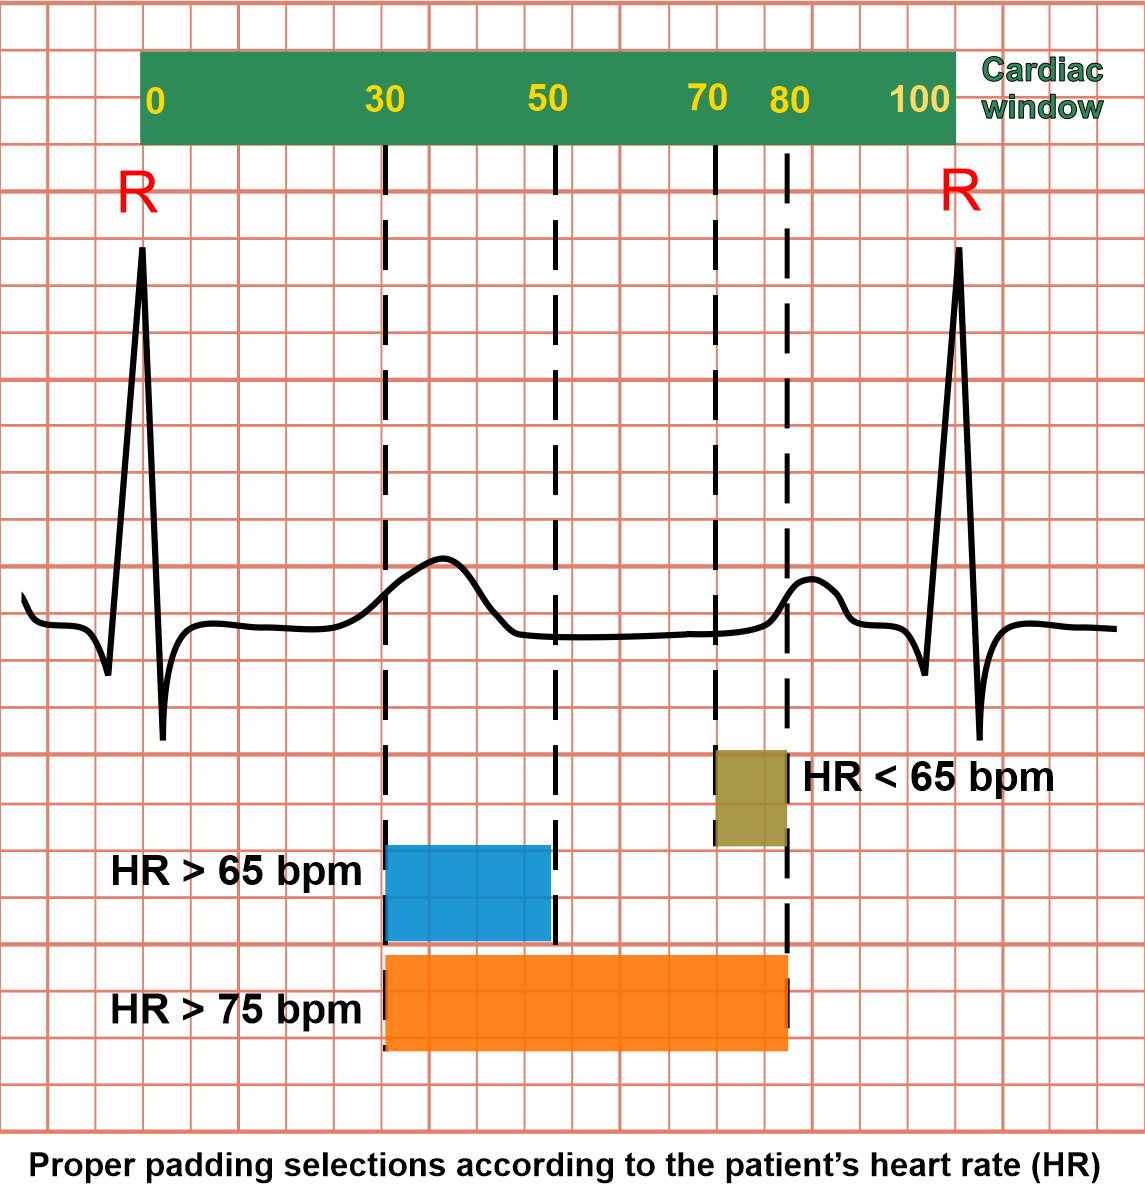

Explanations for cardiac window and gating: as we know, a cardiac cycle can be explained as the set of activities that happens between two adjacent R points (ECG). Simply, there are two major incidents in cardiac cycle which are systole and diastole. In systole, heart muscle contracts and has higher motion than diastole where it relaxes. In order to reduce motion artifacts, we usually obtain images when the heart is in it's least motion (diastolic phase).

The cardiac window is like a ruler that has numbers starting from 0 to 100, and these two ends (0 and 100) are corresponding with two-adjacent-R points (ECG). So, we’re able to select specific parts of cardiac cycle, using these numerical values. For instance, Range 70 to 80 in cardiac window represents end-diastole, and this range selection is called padding.

In CTCA imaging, patient’s heart rate (HR) is one of the major factors that defines image quality as well as radiation exposure. We can reduce the padding for a patient with a lower heart rate and may have to increase it for a higher heart rate. Although by increasing padding or number of exposures (beats), we increase the chance of capturing better images, but it also increases radiation dose.

Mentioned here are the cardiac windows according to the patient’s heart rate:

- Heart rate below 65 bpm – end diastolic (ED), 70-80%

- Heart rate over 65 bpm – end systolic (ES), 30-50%

- Heart rate over 75 bpm – end systolic (ES) to end diastolic (ED), 30-80%